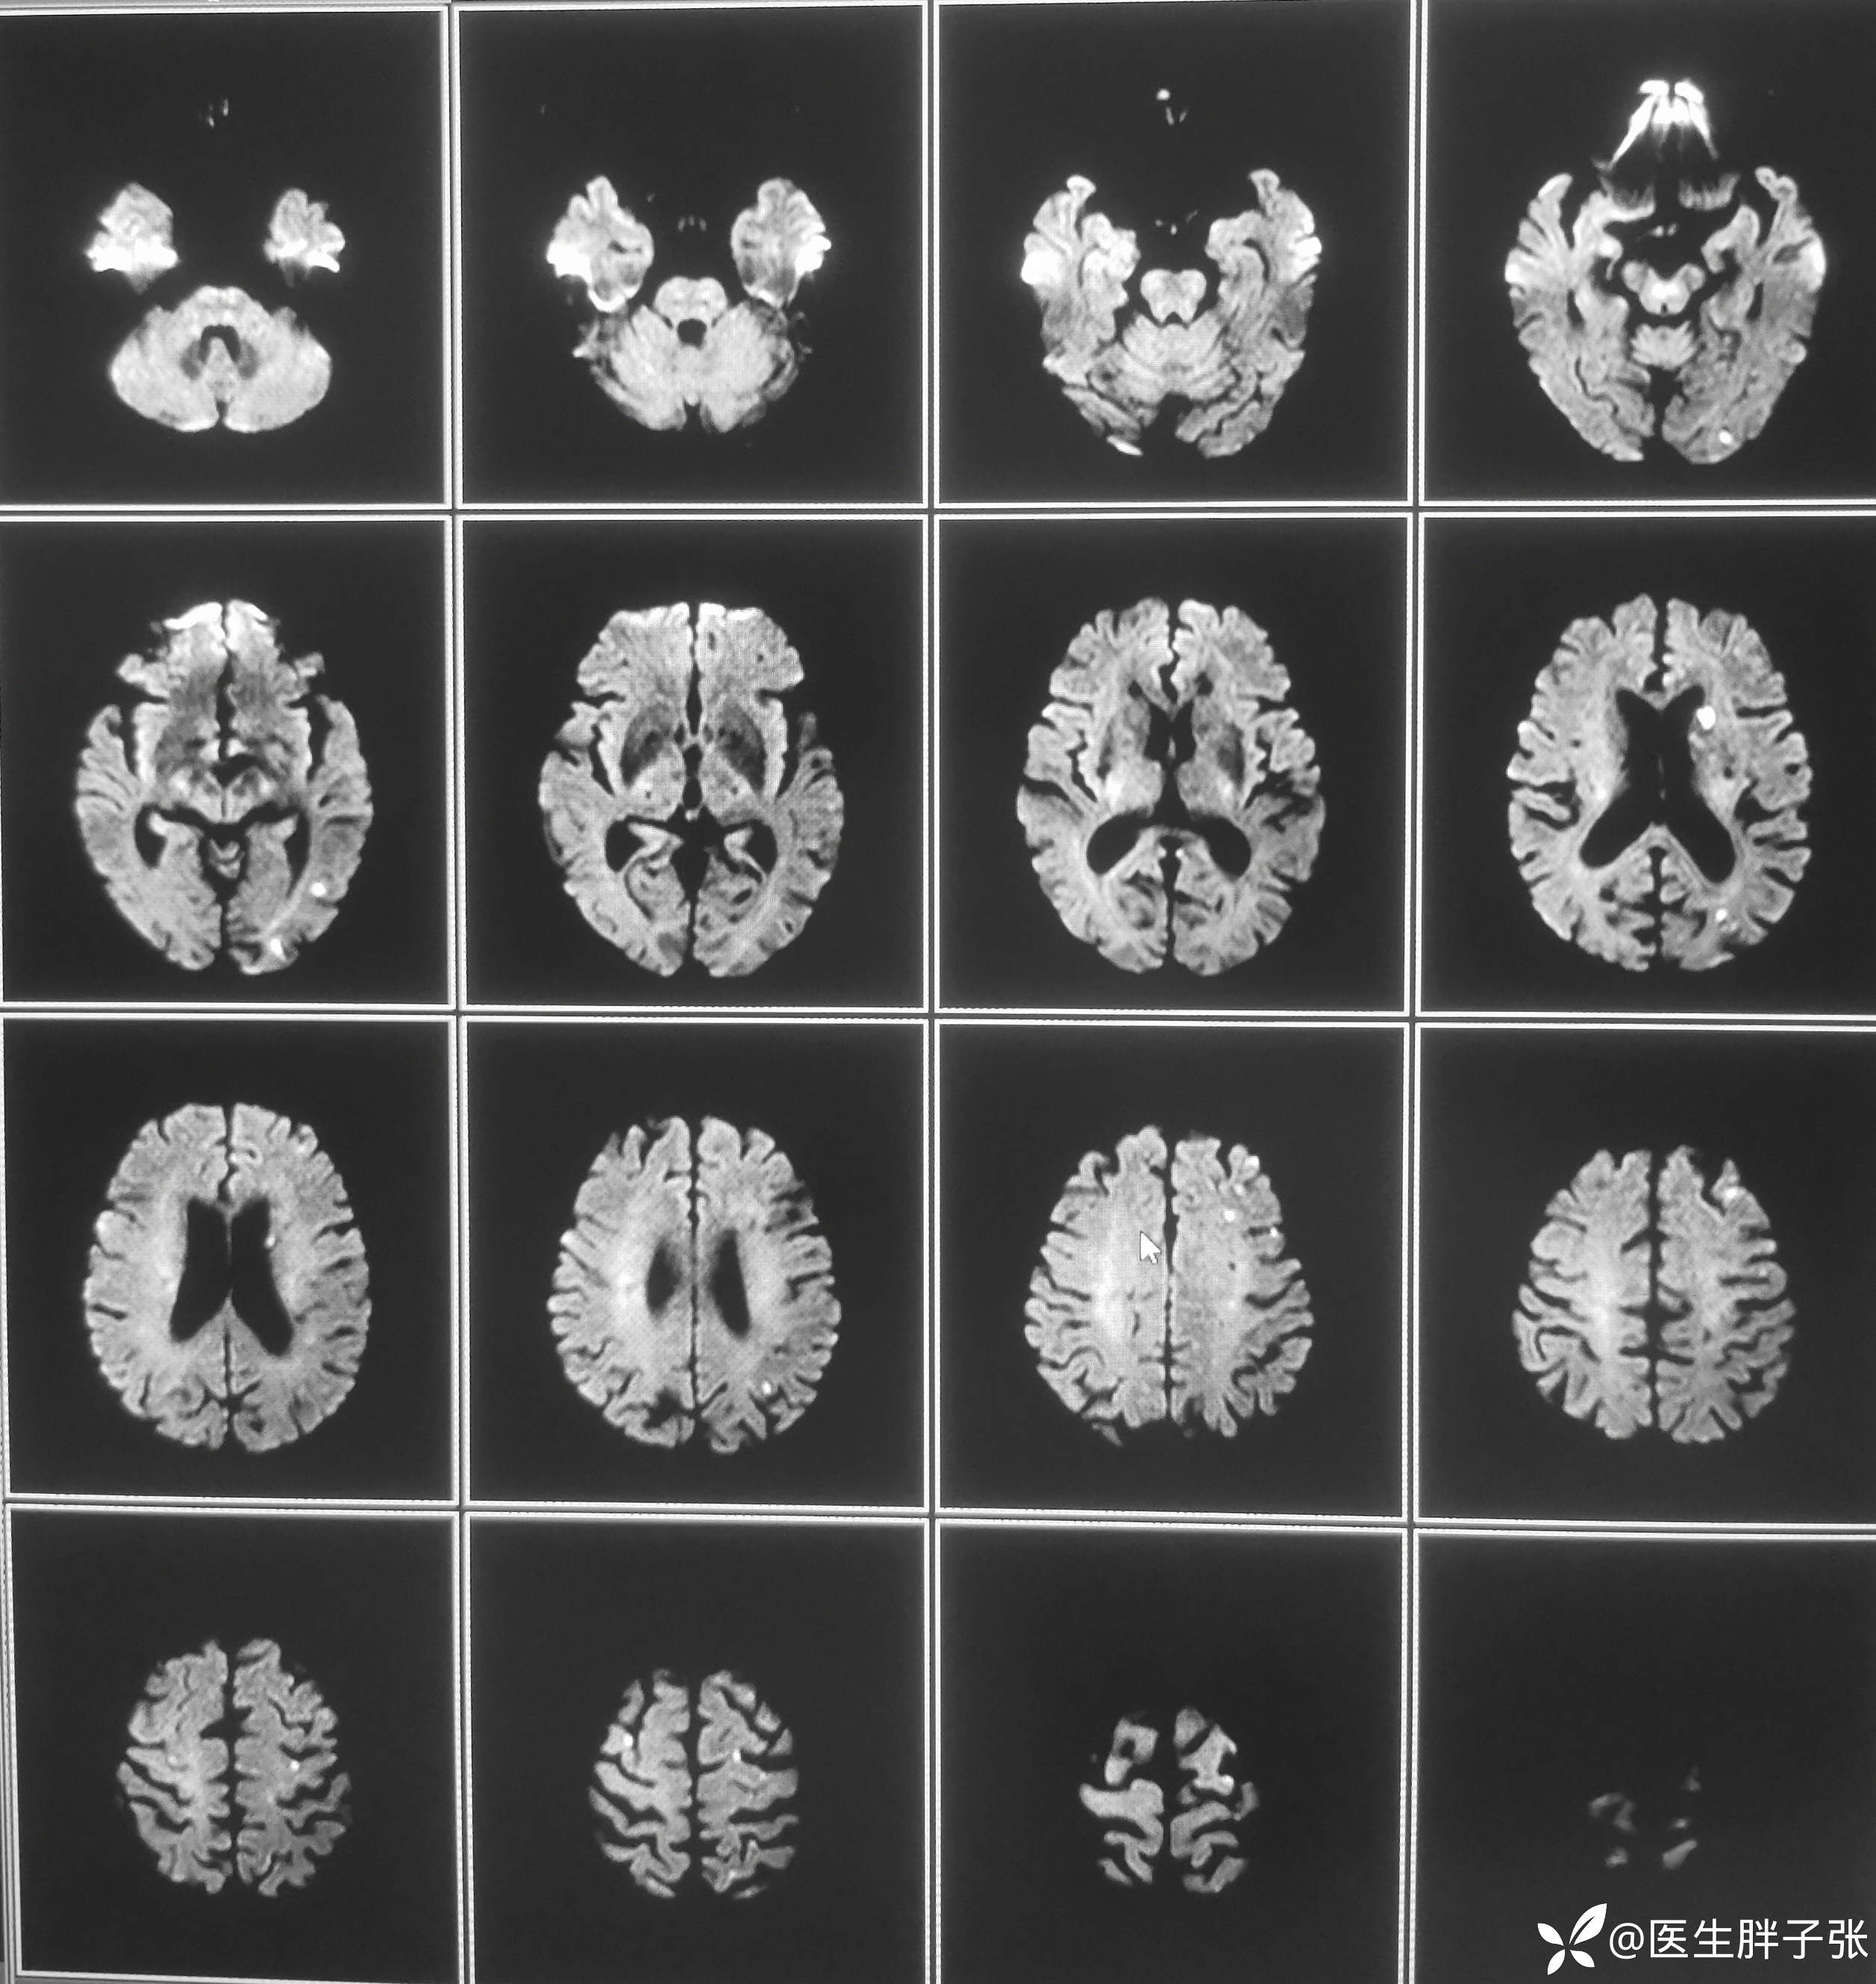

颅脑MR提示左侧枕叶、基底节区、顶叶、双侧额叶新发梗死。